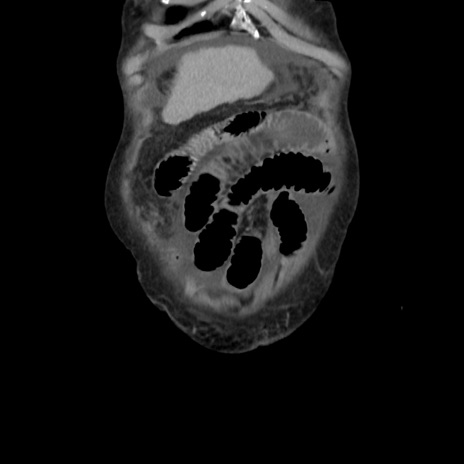

横断像

【症例】80歳代 女性

【主訴】腹部膨満感

【現病歴】他院にて肝硬変にてフォロー中。1週間前から便秘、腹部膨満感、臍部腫瘤あり受診となる。

【既往歴】肝硬変

【身体所見】腹部膨隆あり、皮膚変化なし、疼痛なし。

【データ】WBC 4600、CRP 0.25